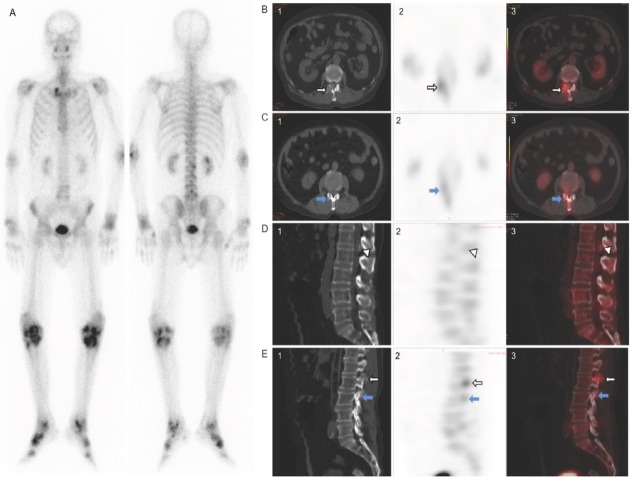

痛风性关节炎,通常简称为痛风,是一种嘌呤代谢紊乱性疾病,其特征是一水尿酸单钠(MSU)结晶沉积在多个系统和器官中,尤其是关节及其周围软组织中。痛风是一种可治疗的慢性疾病,有效治疗的主要策略是通过降低尿酸来逆转 MSU 晶体的沉积,预防痛风发作、痛风石沉积和并发症,从而提高生活质量。然而,痛风经常与其他疾病如高血压、肥胖、心血管疾病、糖尿病、血脂异常、慢性肾脏病(CKD)和肾结石等联系在一起,这可能会使痛风的治疗复杂化,并导致患者过早死亡。在此,我们回顾了医学成像技术在痛风性关节炎研究中的应用,并特别关注单光子发射计算机断层扫描(SPECT)/计算机断层扫描(CT)在痛风及并发症(如慢性肾病和心血管疾病)的临床治疗中的潜在作用。

Gouty arthritis, often referred to simply as gout, is a disorder of purine metabolism characterized by the deposition of monosodium urate monohydrate (MSU) crystals in multiple systems and organs, especially in joints and their surrounding soft tissue. Gout is a treatable chronic disease, and the main strategy for effective management is to reverse the deposition of MSU crystals by uric acid reduction, and to prevent gout attacks, tophi deposition and complications, and thereby improve the quality of life. However, the frequent association of gout with other conditions such as hypertension, obesity, cardiovascular disease, diabetes, dyslipidemia, chronic kidney disease (CKD) and kidney stones can complicate the treatment of gout and lead to premature death. Here, we review the use of medical imaging techniques for studying gouty arthritis with special interest in the potential role of single photon emission computed tomography (SPECT)/computed tomography (CT) in the clinical management of gout and complications (e.g., chronic kidney disease and cardiovascular disease).